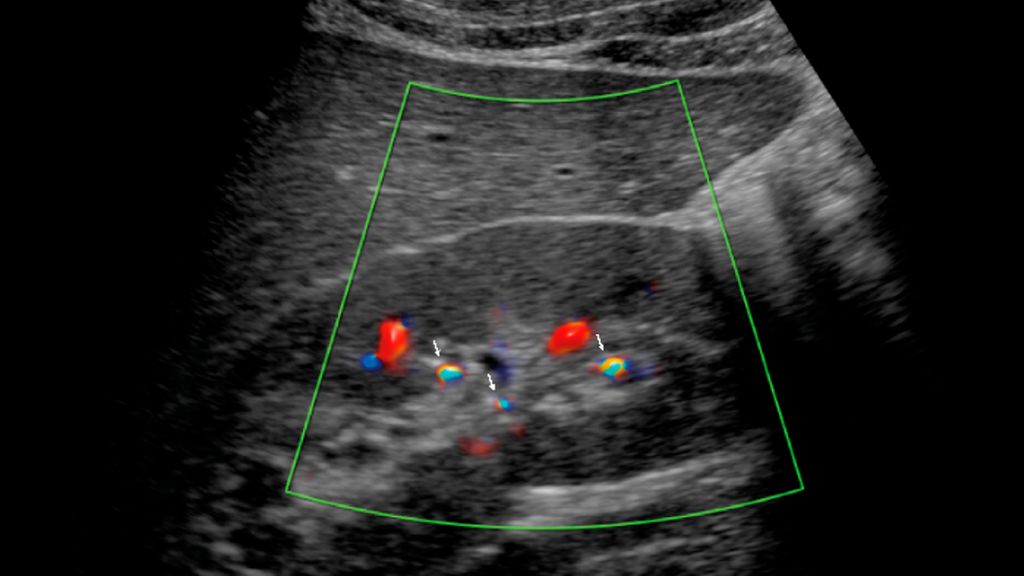

Kinder sind keine kleinen Erwachsenen. Aber kleiner sind sie doch. Aus Sicht des Ureteroskops manchmal zu klein. Die wesentlichen (qualitativen) Unterschiede sind die Symptome und der ...